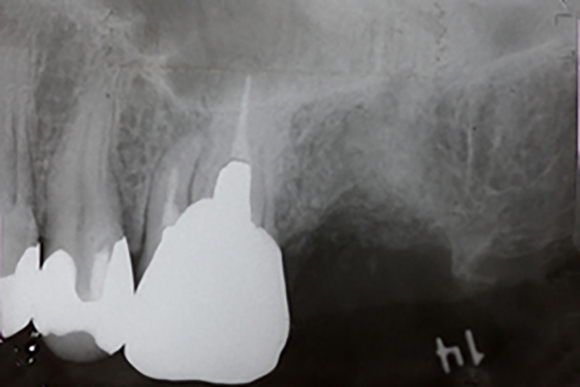

レントゲン写真

左上の一番後ろの奥歯がほとんどで虫歯で抜歯となりました。この部分に対してインプラントをしていくのですが、基本的に上顎には、下顎よりも長めのインプラントを埋入します。その際に上顎には上顎洞という空洞の部分があるのですが、ここには骨がありません。

抜歯後、上のレントゲンでは、右上の方に横に走る白い線が見えます。これが上顎洞の下底になります。そのため、ここに長めのインプラントを埋入すると上顎洞に触れる恐れがありますので、上顎洞の所にインプラントの埋入と同時に骨をつくるのが上顎洞挙上術です。

そこに対して、細い専用の道具でインプラントの入る通路を形成していきます。次のその先端部分から人工の骨を入れて行きます。

上のレントゲンの太い棒の先の部分に上顎洞の下底を貫通して白く顆粒上の物が写っているのが見えます。これが、人工骨を入れた部分になります。この分、インプラントが入るスペースが出来たので、ここに埋入していきます。

こののち6ヶ月ほど骨の成熟とインプラントと骨の結合を待ち、上の被せものを作って行きます。

今回使用したインプラントは、3iの新型インプラントのプリベールというもので、できるだけ周囲の骨が減少しにくくなるように設計されているインプラントです。